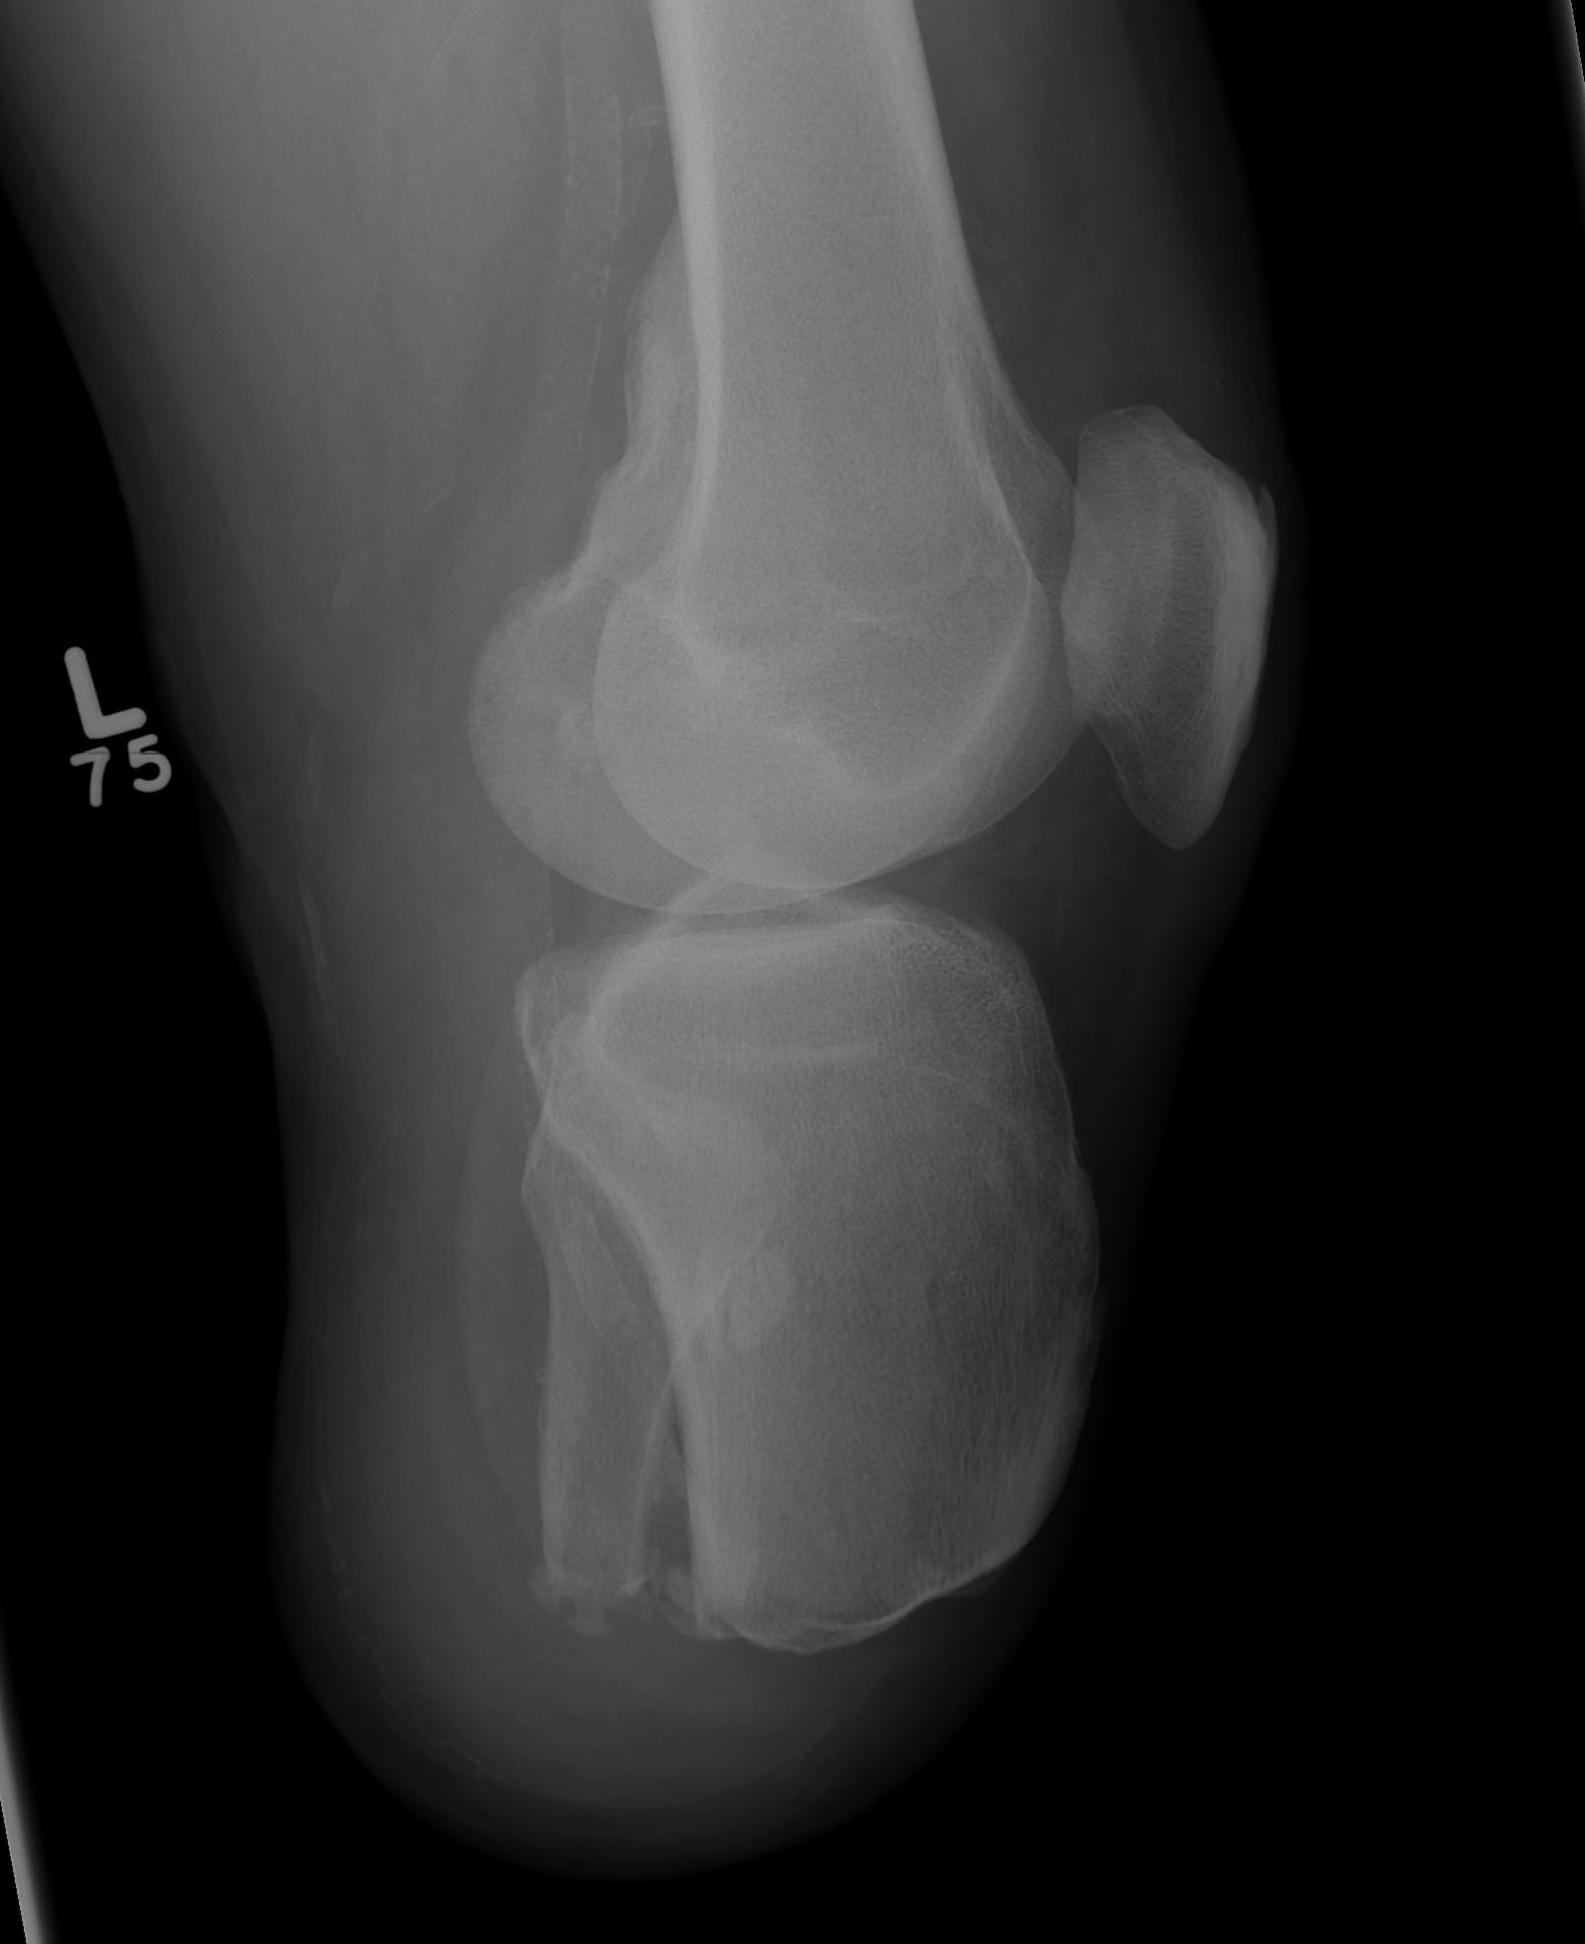

Trans-tibial amputation

www.boneschool.com/amputations-about-the-knee

Technique

Long posterior flap

- keep long tibial stump

- fibular cut 1 - 2 cm shorter

- gastrocnemius myodesis